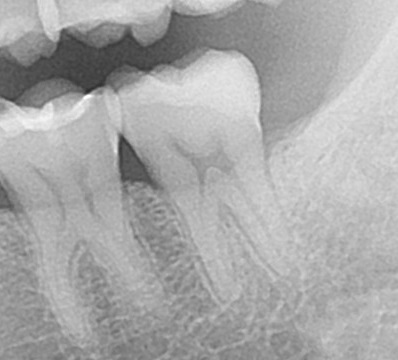

治療1年後のエックス線写真の状態です。

一番奥の歯を治療しましたが、1年以上経過していますが、歯に問題はなく、神経も無事です。